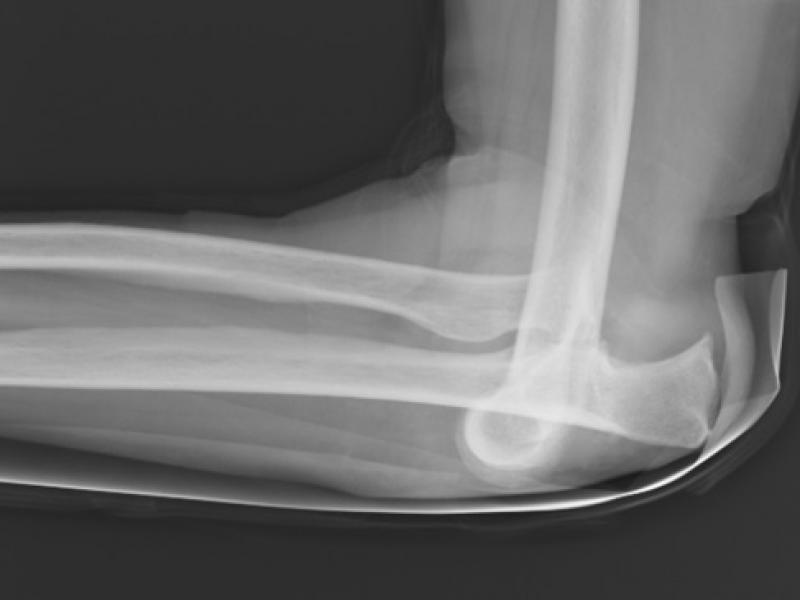

What's the Diagnosis?  By Dr. Erica Schramm

November 28 2018

A 70 year old female with a history of osteoporosis presents